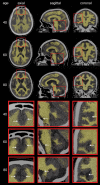

Brain atrophy is correlated with risk of cognitive impairment, functional decline, and dementia. Despite a high infectious disease burden, Tsimane forager-horticulturists of Bolivia have the lowest prevalence of coronary atherosclerosis of any studied population and present few cardiovascular disease (CVD) risk factors despite a high burden of infections and therefore inflammation. This study (a) examines the statistical association between brain volume (BV) and age for Tsimane and (b) compares this association to that of 3 industrialized populations in the United States and Europe. This cohort-based panel study enrolled 746 participants aged 40-94 (396 males), from whom computed tomography (CT) head scans were acquired. BV and intracranial volume (ICV) were calculated from automatic head CT segmentations. The linear regression coefficient estimate β^T of the Tsimane (T), describing the relationship between age (predictor) and BV (response, as a percentage of ICV), was calculated for the pooled sample (including both sexes) and for each sex. β^T was compared to the corresponding regression coefficient estimate β^R of samples from the industrialized reference (R) countries. For all comparisons, the null hypothesis β T = β R was rejected both for the combined samples of males and females, as well as separately for each sex. Our results indicate that the Tsimane exhibit a significantly slower decrease in BV with age than populations in the United States and Europe. Such reduced rates of BV decrease, together with a subsistence lifestyle and low CVD risk, may protect brain health despite considerable chronic inflammation related to infectious burden.